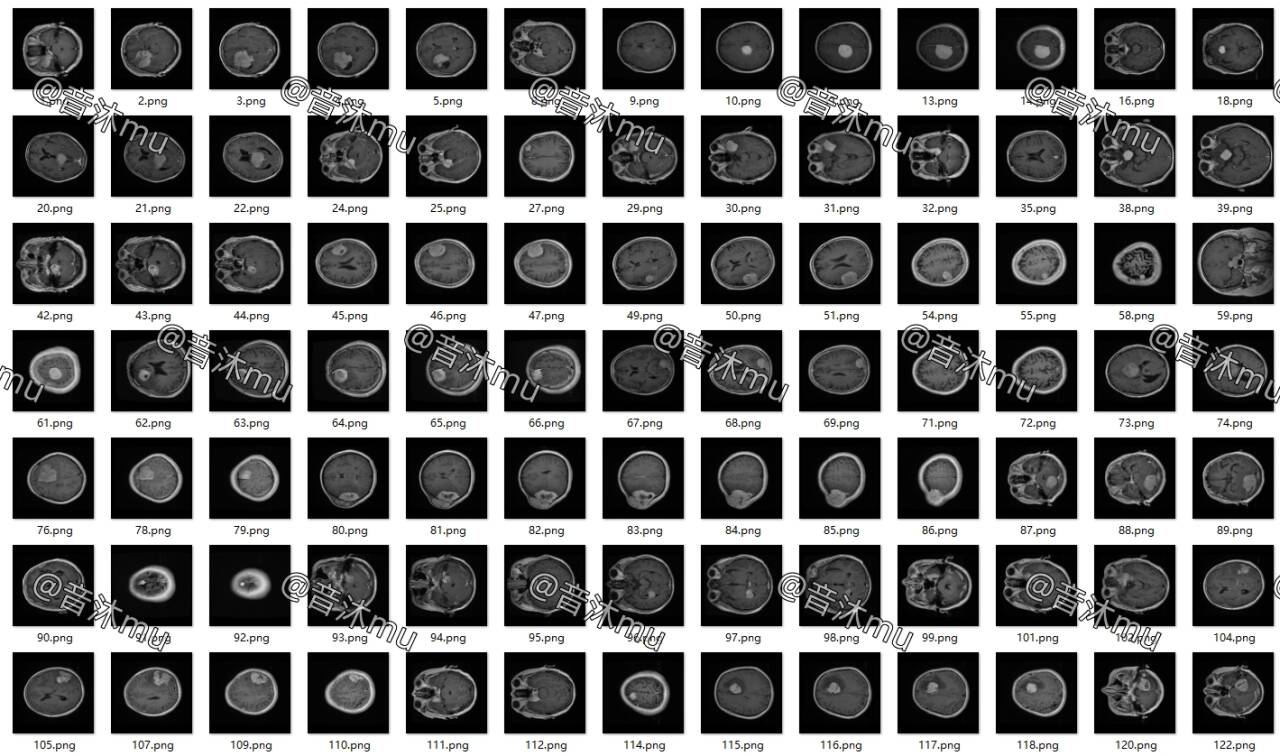

图片数量3064张,已标注txt格式

训练集验证集按2451:613划分可直接用于目标检测训练